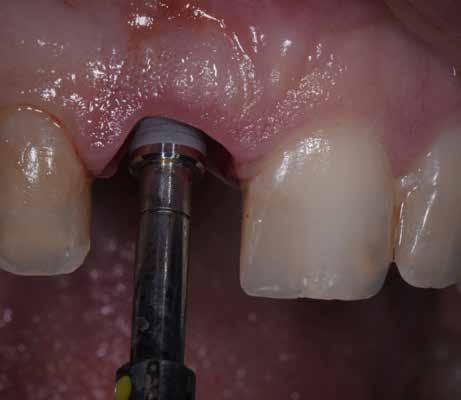

A részleges extrakció befejezése után következhet az implantátumágy preparálása a gyártó utasításai szerint (6.

kép). A bemutatott esetben Nobel Replace CC 4,3x13mm implantátumot helyeztünk be, amely a bukkális oldalon direkt kontaktusba került a megmaradt foggyökérdarabbal (7. kép). Az alveolus oldalfalai és a körszimmetrikius implantátum közötti hézag kitöltésére bovin eredetű xenograftot (Creos S xenogain) használtunk (8. kép). A hasonló

6. kép: Implantátum-ágy preparáció. 7. a–b. képek: Implantátum behelyezés. 8. kép: A behelyezett implantátum. 10. a–b képek: Azonnali ideiglenes korona készítése. 9. kép: Megfelelő primer stabilitás.